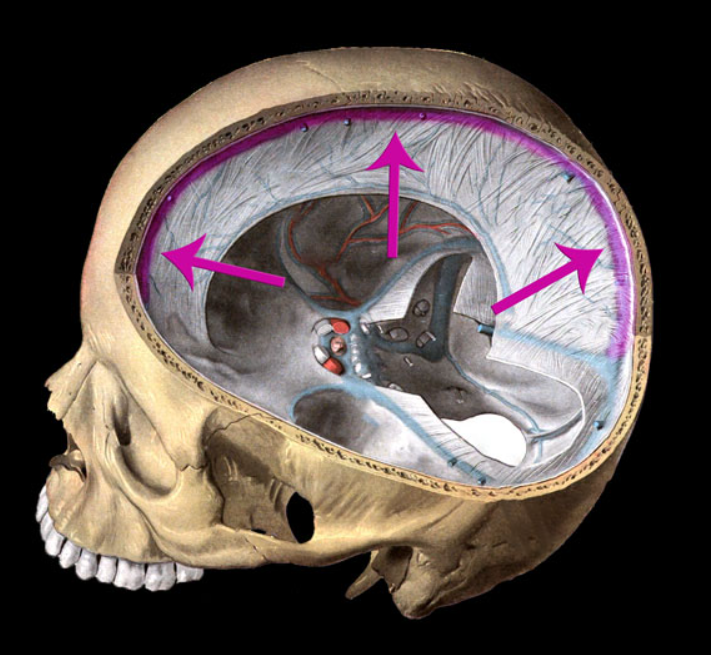

dura mater

arachnoid mater

Pia mater

falx cerebri

falx cerebelli

tentorium cerebelli

dural sinus